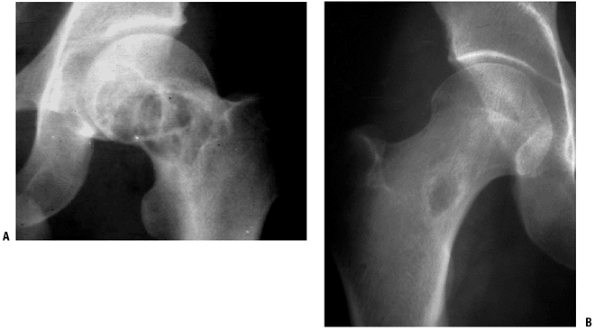

![]() |

Figure 5.5-5 Radiographs of monostotic fibrous dysplasia showing typical ground glass matrix mineralization.

Figure 5.5-6 Histopathology of fibrous dysplasia. Photomicrographs show woven bone trabeculae without osteoblastic rimming.

Figure 5.5-7 Radiographs (A,B) and bone scan (C)

of polyostotic fibrous dysplasia. It usually involves unilateral bones. Note the shepherd’s crook deformity of the proximal femur. |